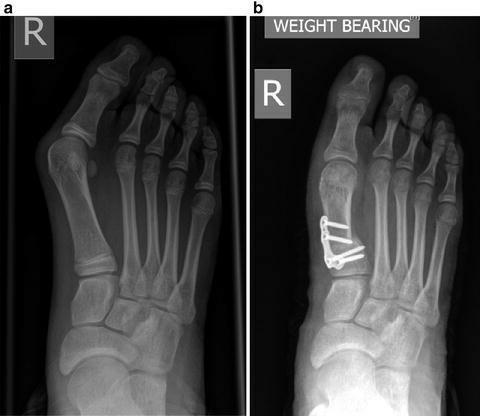

(A)拇外翻角和(B)第1-2跖骨角的测量可以反映拇外翻畸形的严重程度。

拇外翻角:第一跖骨轴与第一近端指骨轴之间。

x线片通过视察第一跖骨和近节趾骨的中轴线之间形成的角度来确定拇外翻的存在。如果角度大于15度,则诊断为拇外翻。45-50°的角度被认为是严重的。同时还应考虑第一节MTP关节内的籽骨移位程度和骨关节炎程度的变化。

如果非手术治疗失败,可以考虑手术治疗。(证据级别:4)在选择手术前,必须确定拇外翻的严重程度。为了做到这一点,使用了负重平片射线照相术。